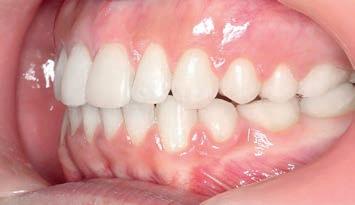

3 months: Class I platform achieved

By the end of the first month of sagittal correction, there was already evidence of some derotation of the upper first molar and movement of the buccal segment (molars, premolars and canines) toward a Class I occlusion. Space was also beginning to open between the upper incisors. After

3 months of sagittal correction, the occlusal lock of the Class I platform had been accomplished (Sagittal First) and the case was ready to progress to the next stage. The Motion appliance was removed. While in this case, it would have been easy to finish the case with Invisalign, the patient chose fixed appliances so Carriere SLX .022 PSL brackets were bonded.

Figs. 9a–c: Situation after 1 month of correction with Sagittal First approach. – Figs. 10a–c: Situation after 2 months of correction. – Figs. 11a–c: Situation after 3 months of correction: Class I achieved. – Figs. 12a–c: Situation after 4 months of treatment (3 months of Motion sagittal treatment and 1 month in fixed appliances). .014 x .025 wire with power chain to close the spaces between the incisors. – Figs 13a–c: Situation after 7 months of treatment (3 months of Motion sagittal treatment and 4 month in fixed appliances). .019 x .025 archwire was engaged with power chain to retract the anterior segment and bring it into the final desired position. – Figs 14a–c: Final situation achieved after 11 months of treatment (3 months of Motion sagittal treatment and 8 months of Carriere SLX fixed appliance therapy).